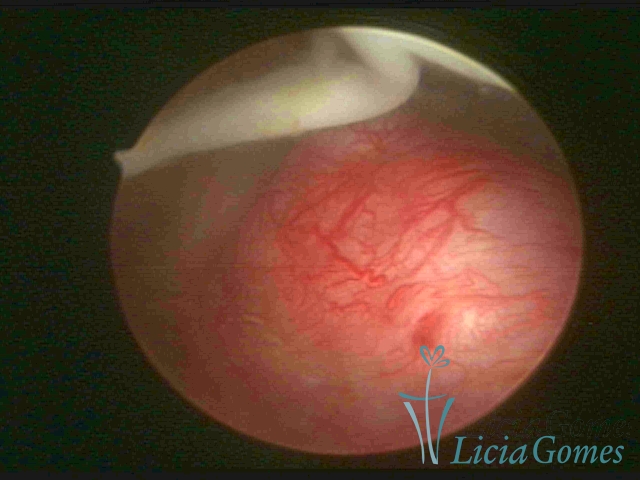

Visão panorâmica de uma cicatriz de cesárea com fio não absorvível há 30 anos